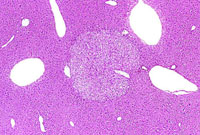

A discrete hepatocellular adenoma with pale staining cytoplasm.